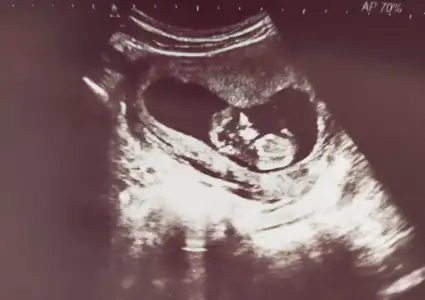

Kıza benzettim benEki Görüntüle 2798000 İyi gecelerbugün bebitoyu gördük kocamaaan olmuşuz doktorumuz cinsiyet tahmini yapabileceğini söyledi ama ben netleşince söyleyin şimdi pat diye kesinmiş gibi hissederim dedim. Sizin bir tahmininiz var mı acaba

![]()